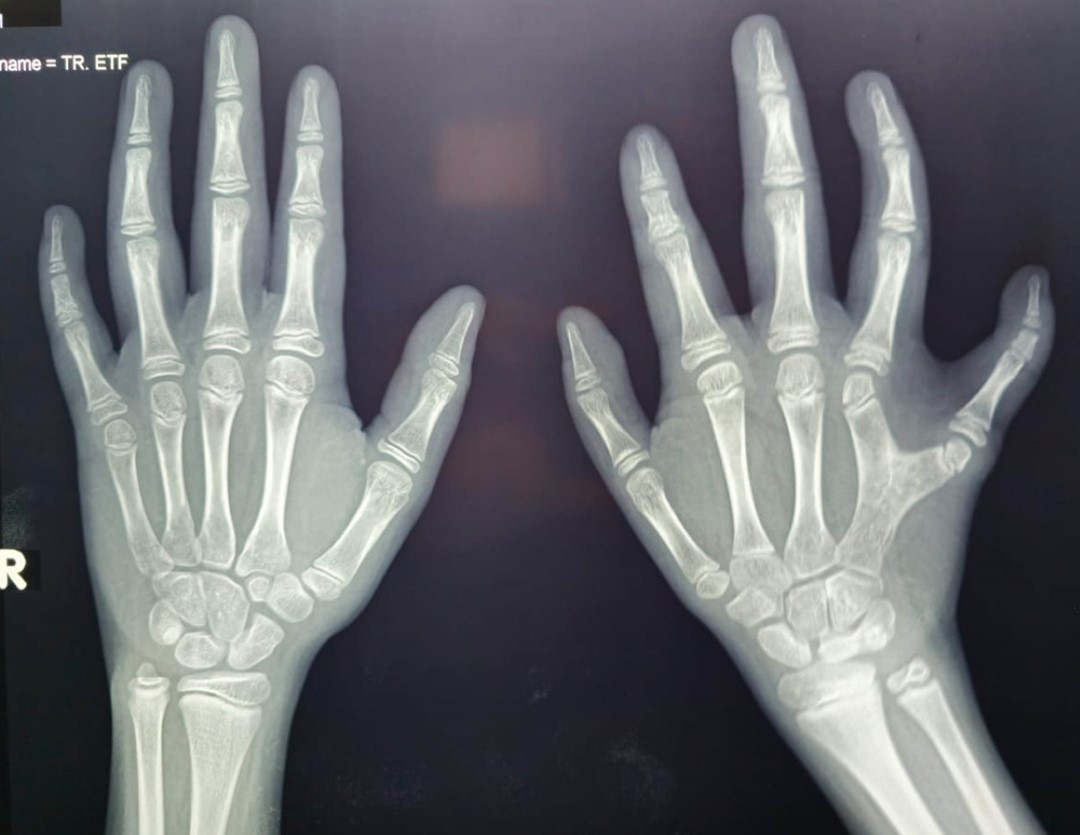

Valoración radiológica: resonancia magnética con secuencias en T1, T2 y FLAIR en planos axial, sagital y coronal, identificando lo siguiente: pérdida de volumen cerebral supratentorial-cortical, en la fosa posterior se observan lesiones extraaxiales, de morfología ovoidea de bordes regulares y bien definidos, hiperintensas en el T2 e hipointensas en el T1 imágenes que sugieren quistes aracnoideos adyacentes al borde posterior de ambos lóbulos cerebelosos, los cuales presentan ligero desplazamiento en sentido anterior e hipoplasia de cuerpo calloso (Figura 2). Radiografías de manos anteroposterior y oblicua que muestran densidad ósea y el estado de mineralización acordes a la edad del paciente, placas de crecimiento acordes con su edad, mano izquierda: se identifica fusión de 4-5 metacarpiano en el tercio proximal y medial, lo que condiciona un desplazamiento en sentido lateral del quinto metacarpiano y medial del cuarto, lo que lleva la pérdida de la morfología habitual de las articulaciones metacarpofalángicas -más evidente en el quinto dedo- con una aparente subluxación con disminución de las dimensiones de los extremos distales de las superficies articulares de los metacarpianos, hay disminución del tamaño, los huesos del carpo más evidente en escafoides izquierdo con disminución en su eje transverso, ausencia de la apófisis estiloides del cúbito izquierdo (Figura 3). Morfología del extremo articular de radio izquierdo presenta un aumento en su eje cefalocaudal, se observa una disminución del espacio articular del semilunar con el piramidal sin descartar la posibilidad de una fusión, asociado a esto hay una disminución de la densidad del piciforme. Radiografías de tórax muestran prominencia del reborde lateral derecho de la silueta cardiaca.

Hasta el momento sólo se había reportado en la literatura manos grandes y carnosas con uñas hipoplásicas o displásicas (en el 34% de los pacientes) en el síndrome del cromosoma 22, éste es el primer caso que reporta malformaciones en manos como lo son la fusión de 4-5 metacarpiano en el tercio proximal y medial y la ausencia de la apófisis estiloides del cubito izquierdo. Esto es una contribución muy importante al fenotipo clínico de los pacientes con anillo del cromosoma 22.

Se concluye que se trata de un paciente con síndrome del anillo del cromosoma 22, con fenotipo clínico que se traslapa con el síndrome de Phelan-McDermid, que es una patología rara y hay pocos casos reportados en la literatura. El espectro clínico del paciente contribuye con características fenotípicas nuevas que no se habían descrito previamente, como lo son la fusión del 4-5 metacarpiano, la ausencia de la apófisis estiloides del cubito izquierdo, la braquidactilia y clinodactilia tipo E del quinto dedo, con sindactilia incompleta del quinto y cuarto dedos tipo V. Adicionalmente se concluye que algunos aspectos de las disfunciones en el gen y los circuitos SHANK3, así como con los fenotipos conductuales, que caracterizan el trastorno del espectro autista y el síndrome de Phelan-McDermid están afectados en el paciente, lo que condiciona su fenotipo clínico.